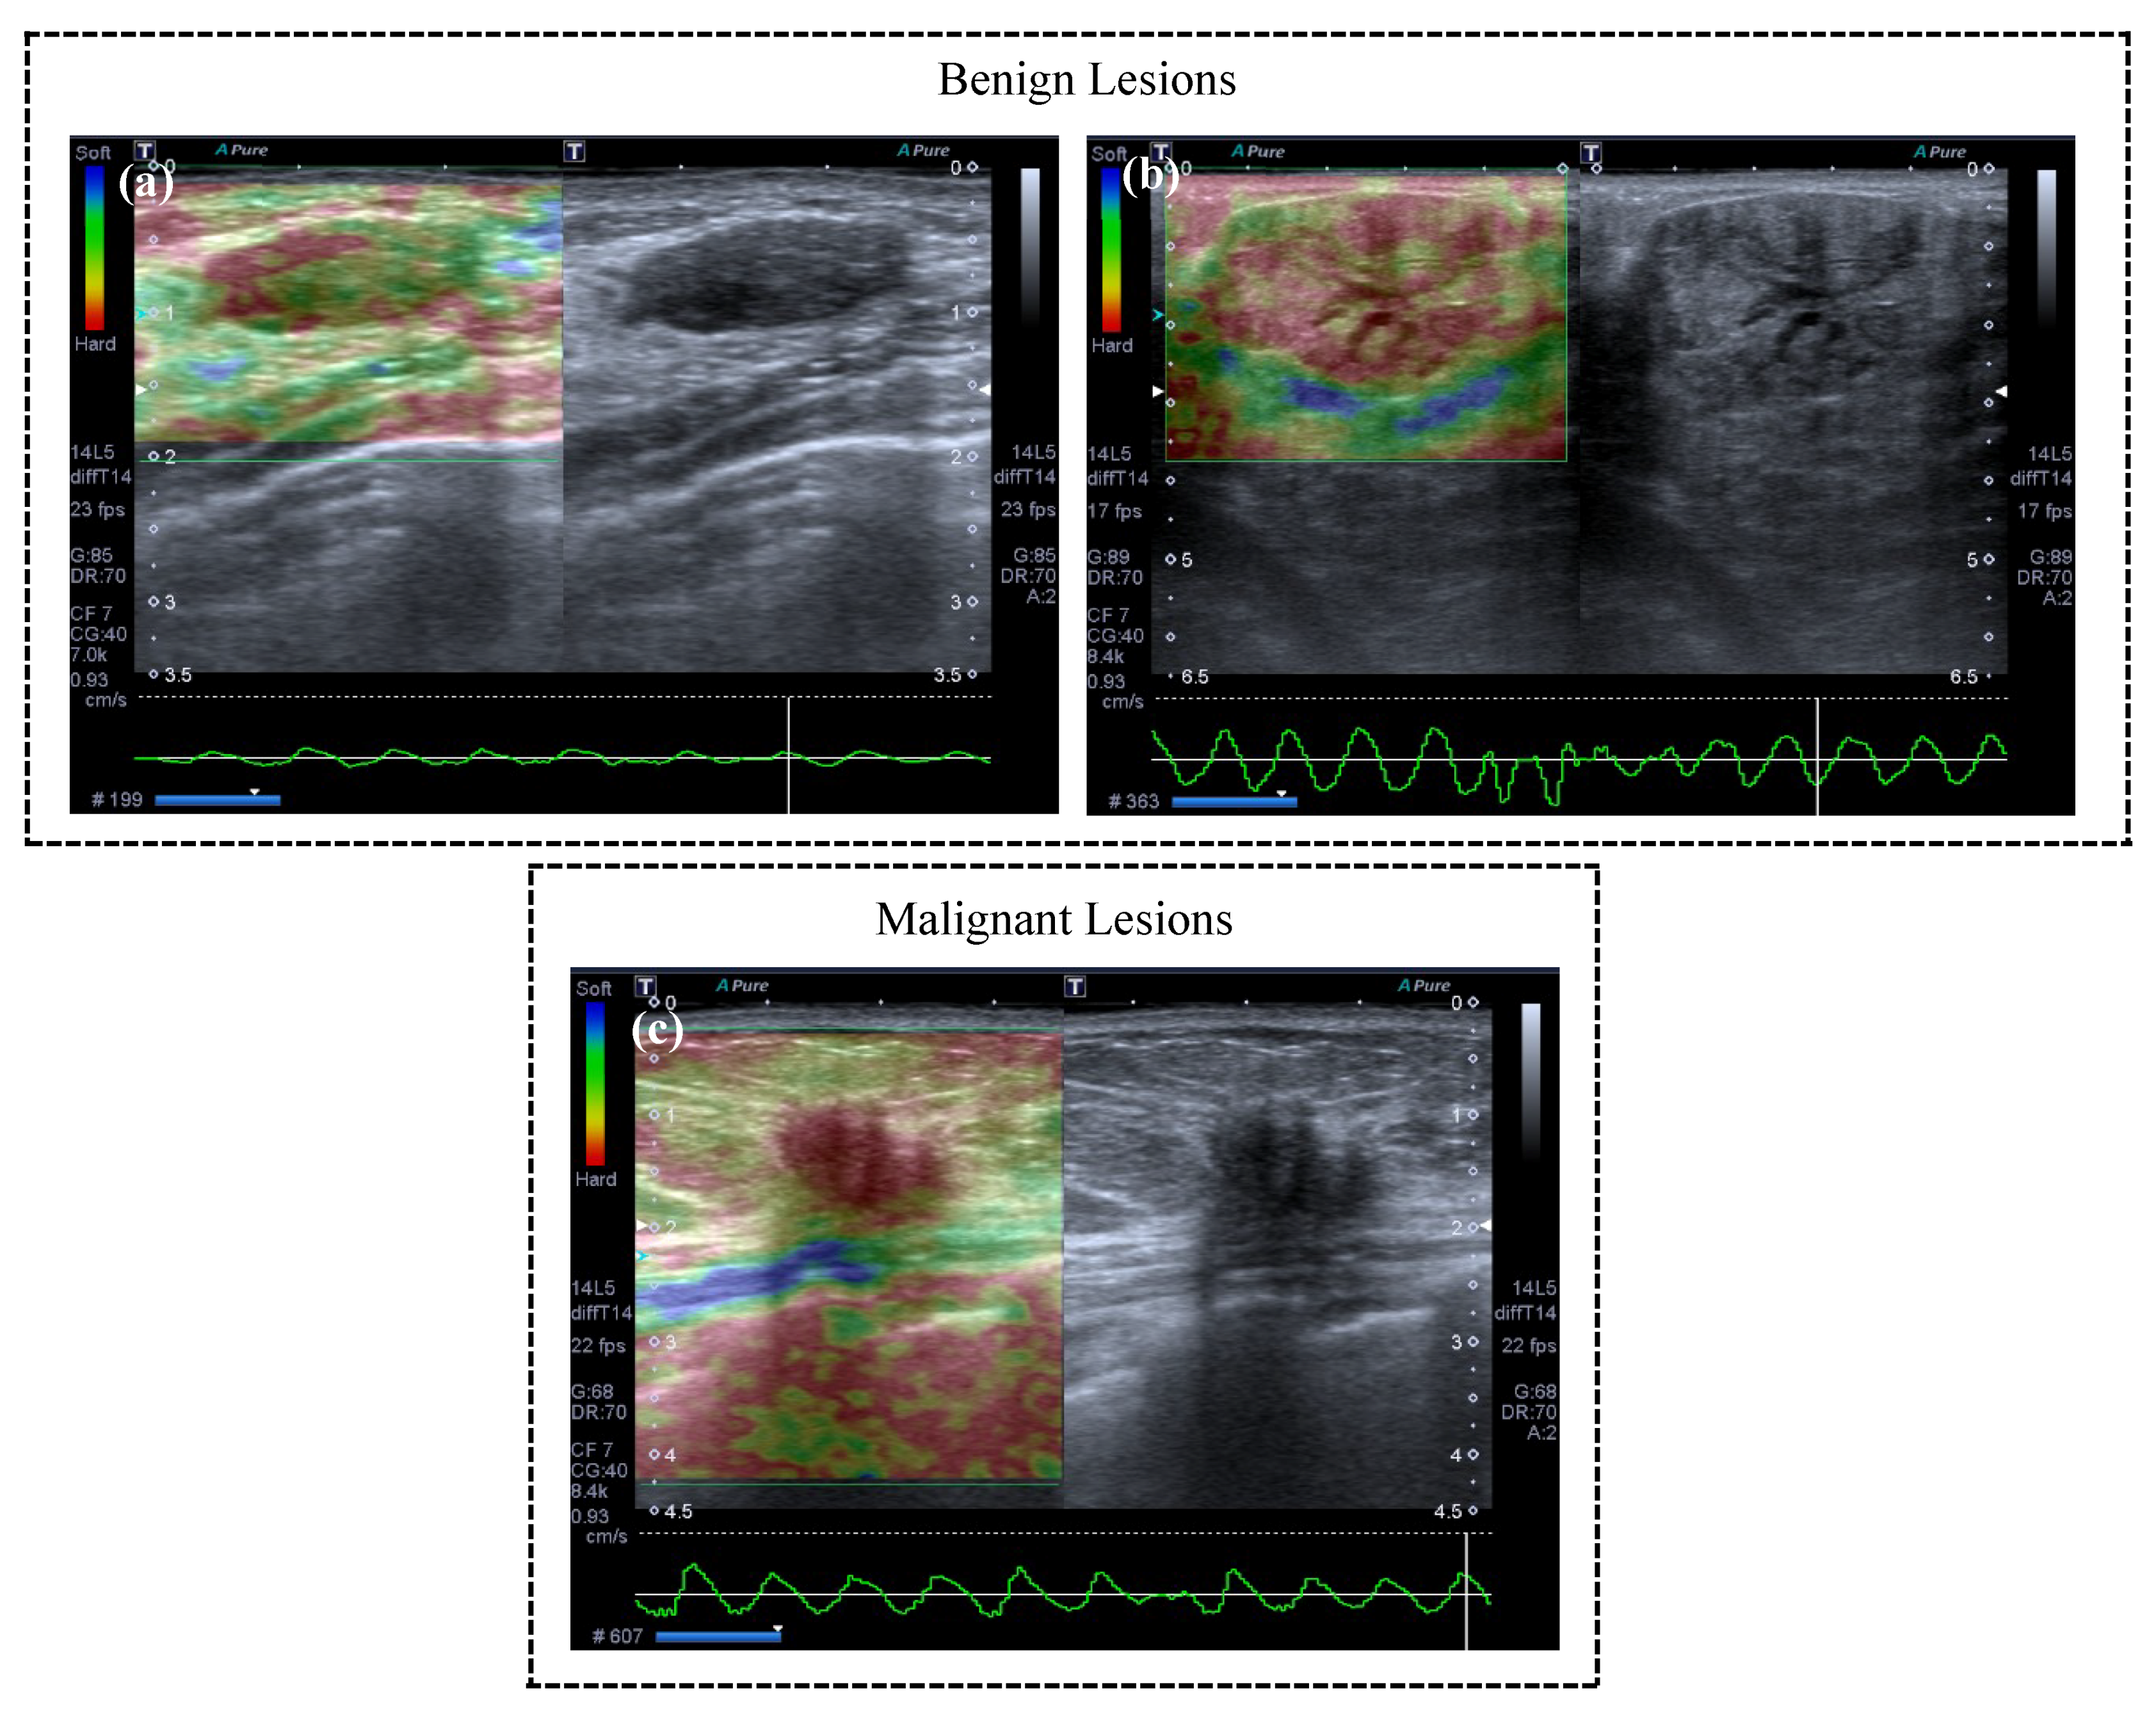

A radiologist with two years of experience performing breast ultrasound examinations obtained the conventional B-mode ultrasound and freehand strain elastography using a Toshiba Aplio 400 Ultrasound System (Toshiba, Tokyo, Japan) with a 5–10 MHz linear transducer. The scanning protocol in this research included transversal, longitudinal, radial, and antiradial real-time imaging of the target lesions with conventional US. The target mass was perpendicularly compressed with a tiny force applied by the transducer. The strain elastography image was superimposed onto the B-mode images with a color scale. The images that best represented the lesions using conventional ultrasound (lesion with the largest axis) and strain elastography (image with best quality standard for analysis according to the quality information of the equipment) were chosen. In the color scale (strain image), blue indicates soft tissue and red indicates hard tissue. B-mode images were on the right side and elastographic images were on the left side, as the examples illustrate in Figure 2.

Figure 2.

Examples of elastography imaging with different strain. The images were visually classified by a radiologist as follows: (a) soft; (b) intermediate; and (c) hard. The radiologist grouped lesions considered as (a) soft and (b) intermediate into negative cases (benign) and (c) hard lesions were classified as positive cases (malignant).